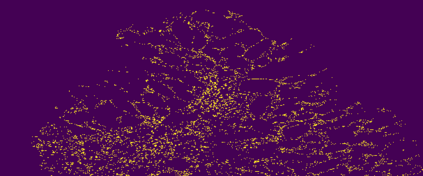

The usage of chemical imaging technologies is becoming a routine accompaniment to traditional methods in pathology. Significant technological advances have developed these next generation techniques to provide rich, spatially resolved, multidimensional chemical images. The rise of digital pathology has significantly enhanced the synergy of these imaging modalities with optical microscopy and immunohistochemistry, enhancing our understanding of the biological mechanisms and progression of diseases. Techniques such as imaging mass cytometry provide labelled multidimensional (multiplex) images of specific components used in conjunction with digital pathology techniques. These powerful techniques generate a wealth of high dimensional data that create significant challenges in data analysis. Unsupervised methods such as clustering are an attractive way to analyse these data, however, they require the selection of parameters such as the number of clusters. Here we propose a methodology to estimate the number of clusters in an automatic data-driven manner using a deep sparse autoencoder to embed the data into a lower dimensional space. We compute the density of regions in the embedded space, the majority of which are empty, enabling the high density regions to be detected as outliers and provide an estimate for the number of clusters. This framework provides a fully unsupervised and data-driven method to analyse multidimensional data. In this work we demonstrate our method using 45 multiplex imaging mass cytometry datasets. Moreover, our model is trained using only one of the datasets and the learned embedding is applied to the remaining 44 images providing an efficient process for data analysis. Finally, we demonstrate the high computational efficiency of our method which is two orders of magnitude faster than estimating via computing the sum squared distances as a function of cluster number.